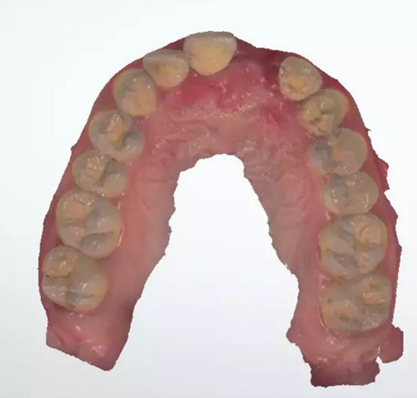

術(shù)前檢查

1.術(shù)前CT